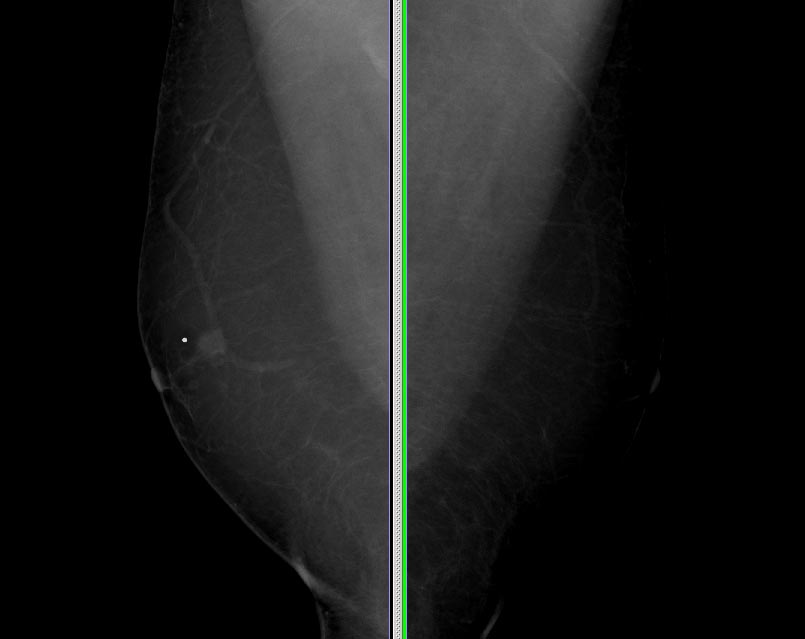

However, for those over 40, medications are more frequently the cause of breast enlargement, and cancer is more prevalent in this age group. As a result, in addition to the standard evaluation, these patients typically undergo a diagnostic mammogram and some form of biopsy. If a benign diagnosis is established, the patient is monitored conservatively. If the diagnosis is cancer, a standard mastectomy is usually performed.

Digital mammogram and male breast cancer: